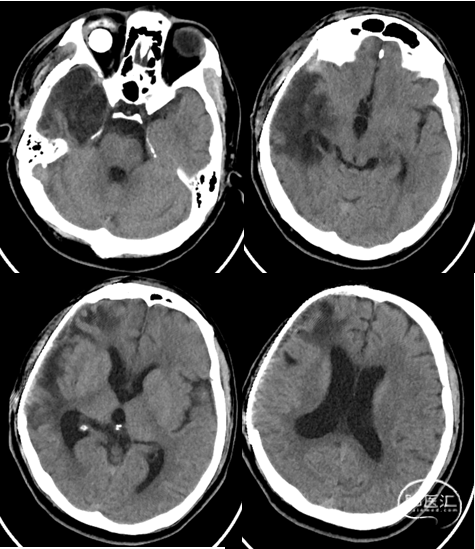

出院时影像

出院时情况

患者偶有烦躁、偏执、哭闹,可遵嘱动作,独立行走,无发热,无呕吐及四肢抽搐,大小便正常。

查体:神志清楚,左侧瞳孔直径2.5mm,对光反射灵敏,右眼眼球摘除术后,头部切口愈合良好,骨窗压力不高,双肺呼吸音粗,未闻及啰音,腹软,左侧肢体肌力4+级,右侧肢体肌力5级,肌张力正常,生理反射存在,病理反射未引出。